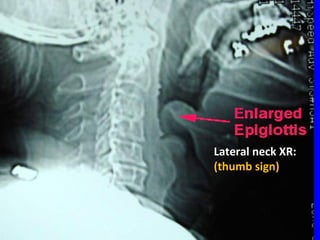

EXAMINATIONEXAMINATION • Do notDonot examine the throatexamine the throat • Assess severityAssess severity – degree of stridor, resp. rate, HRdegree of stridor, resp. rate, HR – pulse oximetry, arousalpulse oximetry, arousal • Dx:Dx: – ““cherry red” epiglottischerry red” epiglottis – ‘‘thumb sign’ on lateral neck XRthumb sign’ on lateral neck XR – blood cultures, electrolytesblood cultures, electrolytes

Lateral neck XR:Lateralneck XR: (thumb sign)(thumb sign)